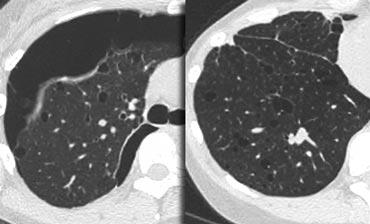

LEFT: No fibrosis, so potentially treatable lung disease. RIGHT: Fibrosis, so no treatable lung disease.

Có thể điều trị hay không thể điều trị?

Mặc dù GGO không đặc hiệu, đây là một dấu hiệu có ý nghĩa quan trọng: 60–80% bệnh nhân có GGO trên HRCT mắc bệnh phổi đang hoạt động và có khả năng điều trị được.

Trong 20–40% trường hợp còn lại, GGO phản ánh tình trạng xơ hóa và bệnh không thể điều trị được.

Trong những trường hợp này, các dấu hiệu xơ hóa đi kèm trên HRCT thường hiện diện, chẳng hạn như giãn phế quản do co kéo và tổ ong.

Ví dụ

Các hình ảnh cho thấy hai trường hợp có GGO: một trường hợp không có xơ hóa (có khả năng điều trị được) và một trường hợp có giãn phế quản do co kéo (cho thấy có xơ hóa).